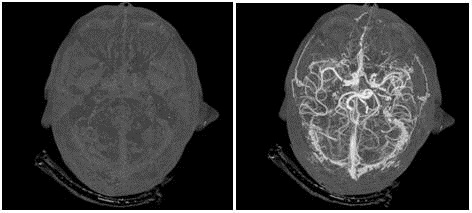

در این روش پرتوهای ایکس وارد بدن بیمار شده و رایانه، تصویر بسیار دقیقی از هر بخش تهیه میکند؛ بطورمثال امکان تهیه تصویر کامل از قلب در مدت تنها یک ضربان قلب فراهم میشود.

این روش توموگرافی رایانهای اشعه ایکس نیز نامیده میشود که اغلب در بیمارستان برای مشاهده تومورها، شکستگی استخوان و خونریزی داخلی استفاده میشود.

عروق، روده، قلب، مغز، استخوانها با جزئیات منحصربفردی به تصویر کشیده میشوند.